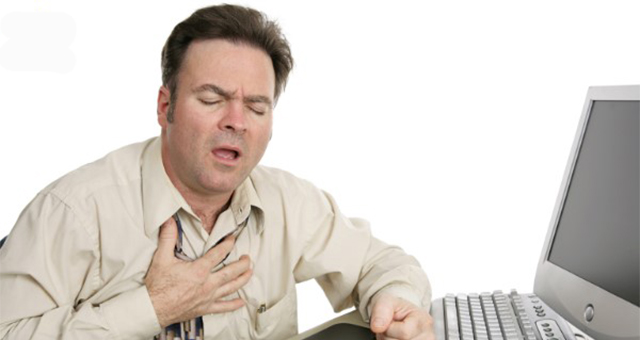

Megjithëse simptomat e një sulmi në zemër mund të jenë të theksuara dhe të qarta sidomos te burrat, ndonjëherë trupi ofron të dhëna më të ndërlikuara për të treguar se diçka nuk shkon me zemrën.

Ne ua sjellim disa nga simptomat, por duhet të keni parasysh se këto simptoma mund të tregojnë një numër sëmundjesh të tjera ose lodhje të trupit, në mënyrë që diagnoza e saktë të jepet vetëm nga një mjek.